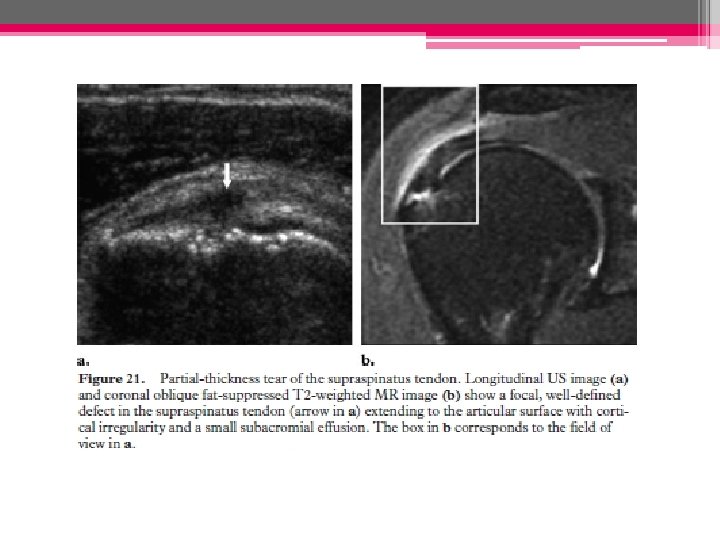

• Rupture partielle (non transfixiante): - Zone hypoéchogène ++ hyperéchogène entourée d’une zone hypo hyper - Face articulaire (profonde)/bursale (superficielle)/ intra-tendineuse

◊ Ruptures partielles profondes

◊ Ruptures partielles superficielles: